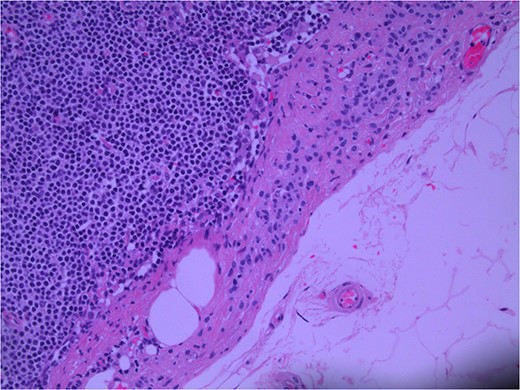

Lymph node specimens were sent for haematoxylin and eosin (H&E) staining (Fig. 3) and IHC analysis. The sections showed mild reactive changes and benign intracapsular nevoid rests. IHC analysis showed that these cells were negative for HMB-45 (Fig. 4) and were positive for both Sox10 and p16 (Figs 5 and 6). Consensus at the Multidisciplinary Team Meeting was that the appearance was in keeping with benign naevoid rests as opposed to melanoma deposits, given the location of the cells, morphology and immunohistochemistry. Surveillance was recommended.

Lymph node; nevoid melanocytes in subcapsular region; H&E × 200 magnification.